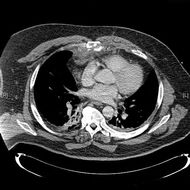

복장뼈는 흉부의 전면에 위치한 길쭉한 편평골로, 빗장뼈와 갈비뼈의 갈비연골에 연결되어 흉곽을 구성하는 중요한 뼈이다. 위에서부터 복장뼈자루, 몸통, 칼돌기로 구성되며, 성인의 경우 남성이 여성보다 약간 더 길다. 흉골자루, 몸통, 칼돌기는 각각 쇄골, 갈비뼈, 심장막인대 등과 연결되어 있으며, 흉골각, 흉골공, 부흉골과 같은 해부학적 변이가 나타날 수 있다. 흉골은 골수 검사, 심장 흉부 외과 수술, 골절 치료 등에 사용되며, 흉골 골절은 외상이나 반복적인 타격으로 발생할 수 있다. 흉골은 척추동물, 특히 조류와 포유류에서 다양한 형태로 나타나며, 절지동물에서도 발견된다. 'sternum'이라는 영어 단어는 고대 그리스어 'στέρνον'에서 유래되었으며, '단단한' 또는 '견고한'을 의미한다.

복장뼈는 흉부의 앞면에 있는 길쭉한 편평골이다. 복장뼈 윗부분은 빗장뼈와 관절을 이루며 지지하고, 그 가장자리는 첫 7쌍의 갈비뼈의 갈비연골과 붙어 있다. 복장뼈 안쪽 표면은 복장심장막인대와 연결되어 있고, 가장 윗부분은 목빗근과도 연결되어 있다.

복장뼈는 좁고 납작한 뼈로, 가슴 앞쪽의 중간 부분을 형성한다. 자연스러운 자세에서 복장뼈는 비스듬히 아래쪽과 앞쪽으로 기울어져 있다. 앞쪽은 약간 볼록하고 뒤쪽은 오목하다. 위쪽은 넓고 "T"자 모양이며, 자루가 몸통과 연결되는 지점에서 좁아진 다음, 몸통의 중간 부분 아래까지 다시 약간 넓어지고, 아래쪽 끝으로 갈수록 좁아진다. 성인의 경우 복장뼈는 평균적으로 남성이 여성보다 약 1.7cm 더 길다.